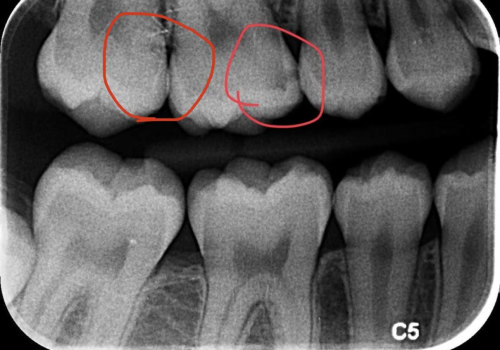

What causes you to need a root canal?

Endodontics are necessary for a fractured tooth due to injury or genetics, deep decay, or problems caused by a previous...